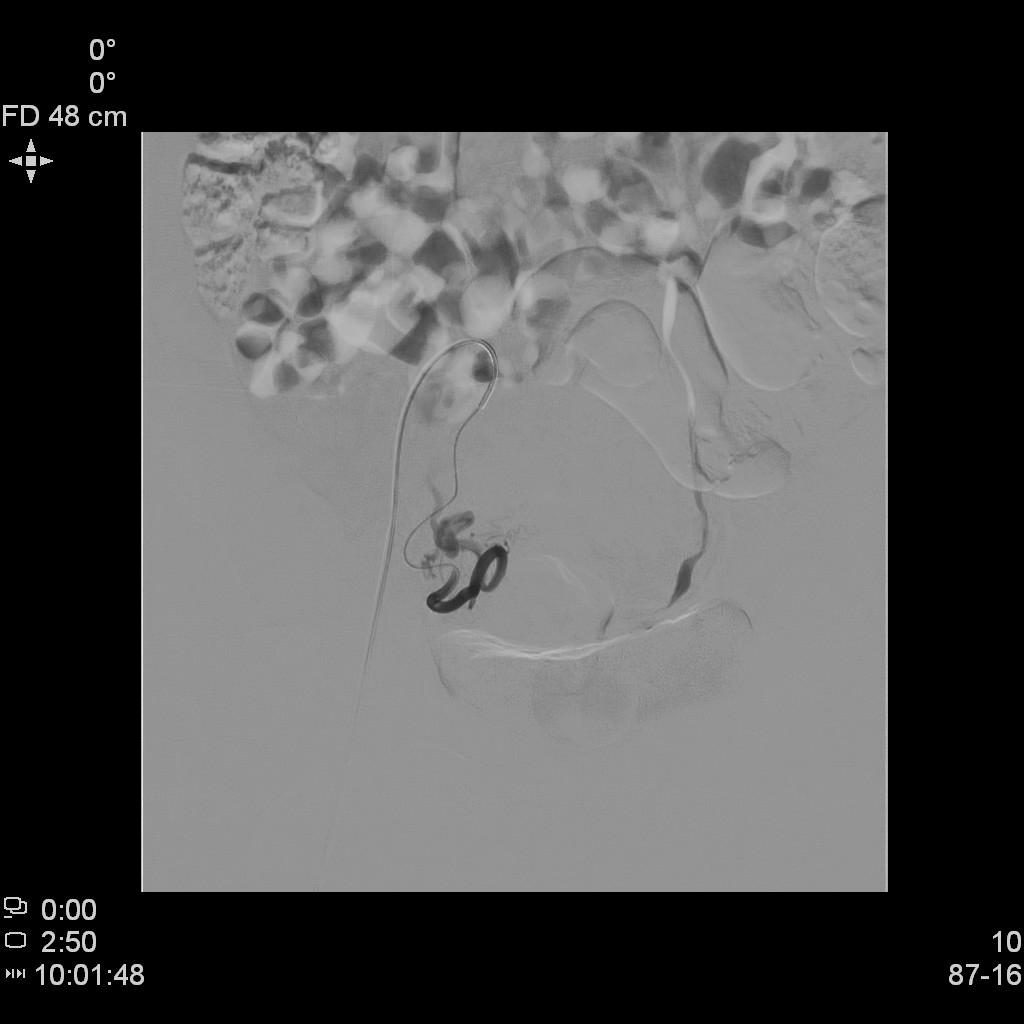

- 进一步超选插管左侧髂内动脉造影确认子动脉开口位置。

左侧髂内动脉造影

- 微导管进一步超选插管左侧子宫动脉主干造影确认位置。

左侧子宫动脉造影

- 术后桡动脉止血器压迫止血8小时,患者术后无需长时间卧床、下肢制动,舒适度大大提升,利于术后快速康复。

桡动脉压迫止血器